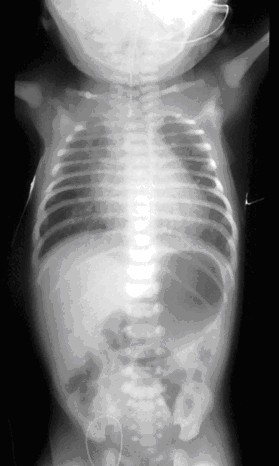

흉부와 복부의 단순 X선 영상. 영양관이 폐쇄된 식도를 지나가지 못하고 있다

폐쇄가 일어난 부분 위쪽의 상부 식도에 조영제가 들어간 것을 보여주는 단순 X선 촬영 영상.

단순 X선 영상에서는 영양관이 식도를 통과하지 못하고, 상부 식도에 꼬인 채로 남아 있게 되는 모습을 발견할 수 있다.[39][11]